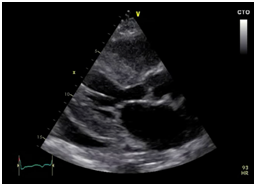

Subsequently, she was admitted to our institution with a clinic diagnosis of acute heart failure, Stevenson B. A chest X-ray showed bilateral pleural effusion, grade II. During the admission, the only significant finding was mild anemia (Hb 11,1g/dl). A transthoracic echocardiogram (Figure 1 & Video 1) was done showing normal left ventricle diameters, LV ejection fraction 47%, mild concentric hypertrophy, biatrial enlargement, mild to moderate mitral regurgitation, pseudo normal ventricular filling pattern, e 4cm/sec, E/e´ ratio greater than 18, moderate tricuspid insufficiency, an estimate pulmonary artery systolic pressure of 55mmHg and mild pericardial effusion. The presumptive diagnosis of infiltrative restrictive cardiomyopathy was assumed. A myocardial 3D strain imaging with speckle tracking was done, showing normal longitudinal strain of apical segments and a strong impaired values of basal and mid segments (-16 to -28 at apical segments vs 4 to -4 at basal level) (Figure 2C). The patient improved clinically with diuretics and vasodilators according to local guidelines. Nevertheless, during the third day of hospitalization she experiences a sudden death episode, with ventricular tachycardia documented in the telemetric system, with an adequate response to cardiopulmonary resuscitation (CPR).

Figure 1 We can see a parasternal long axis view (A), short axis at mid ventricular level (B) and 4 chambers (C), showing mild hypertrophy (12mm) with biatrial enlargement and mild pericardial effusion (White arrow).

Video 1 parasternal long axis, shot and apical axis view. 2D, color doppler, showing mild hypertrophy with biatrial enlargement, mild pericardial effusion, mild to moderate mitral regurgitation, moderate tricuspid regurgitation, inferior cava vein dilated.